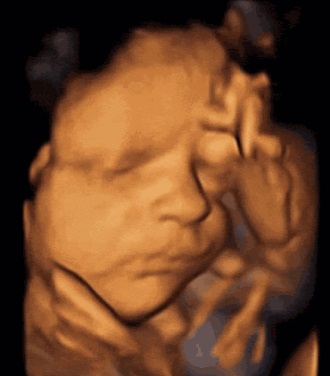

怀胎十月,需要经历多次的产检,四维彩超是最常见的大排畸检查,不仅能够排查胎儿畸形,还能够看到胎儿的动态图片,拍照留念。但是四维彩超在排畸的时候,也需要胎儿的配合,如果胎儿配合不好,无法很全面的看到胎儿发育情况。今天,福兴医生就为准爸妈讲解几个常见的原因。>>>我想直接了解什么原因?

那胎儿为什么这么喜欢捂着脸呢?